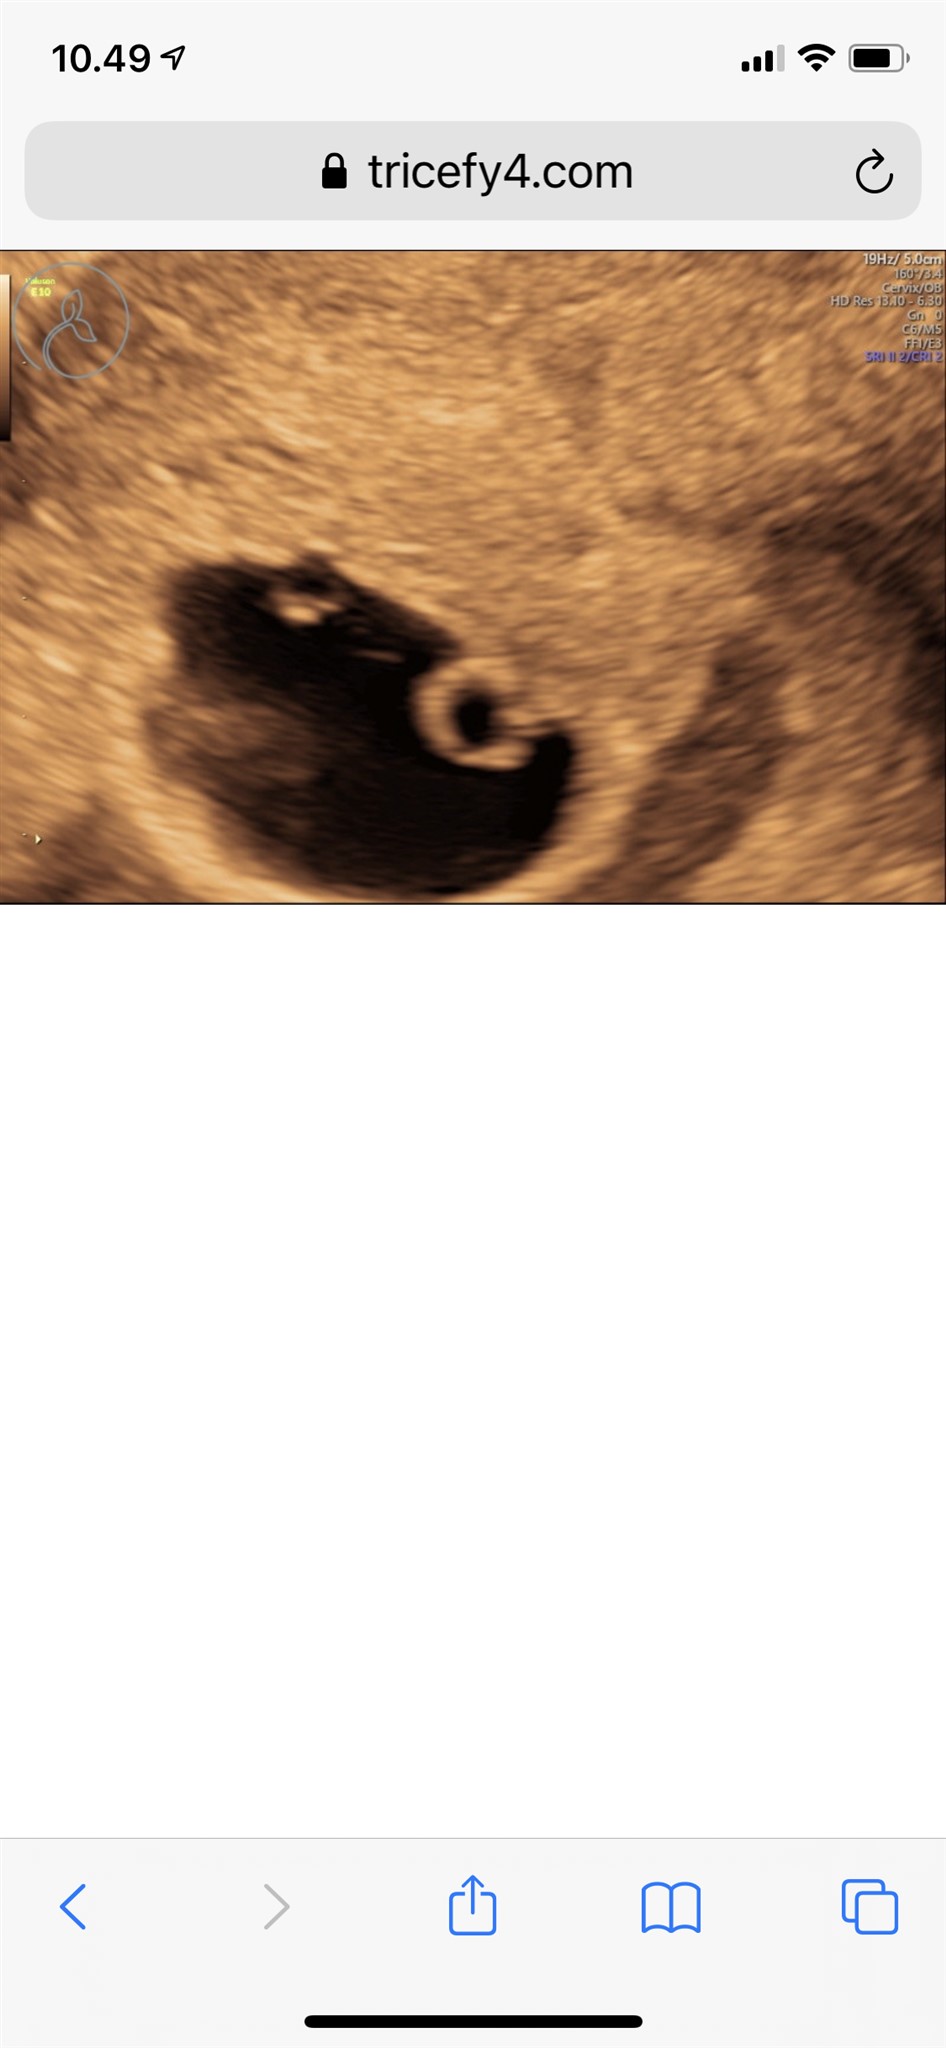

Der var ikke noget foster endnu, men der var sket udvikling i gestationssækken og blommesækken  Så vi kan bare vente på blodprøver i morgen, og se om der er sket en stigning

Hej igen trådstarter

Jeg var til scanning igen i dag, og nu var der pludselig anlæg til et foster, dog ikke hjerteblink endnu.. Så jeg har fået taget en blodprøve igen igen, for at se om der er stigning eller hvad der sker.

Så var der også hjerteblink her i dag. Så virker til vi er ude i et ens forløb